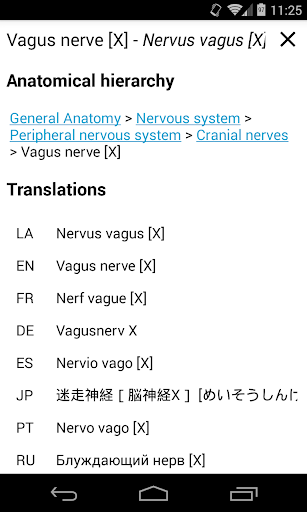

e-Anatomy tiene más de 26 000 imágenes que contienen series de imágenes en vistas axiales, coronales y sagitales, así como radiografías, angiografías, imágenes de disección, gráficos anatómicos e ilustraciones. Todas las imágenes médicas fueron etiquetadas cuidadosamente, más de 967 000 etiquetas disponibles en 12 idiomas, incluida la Terminologia Anatomica latina.

- Cambie de idioma con solo tocar un botón

. *Navegación entre partes anatómicas usando enlaces de descripción.